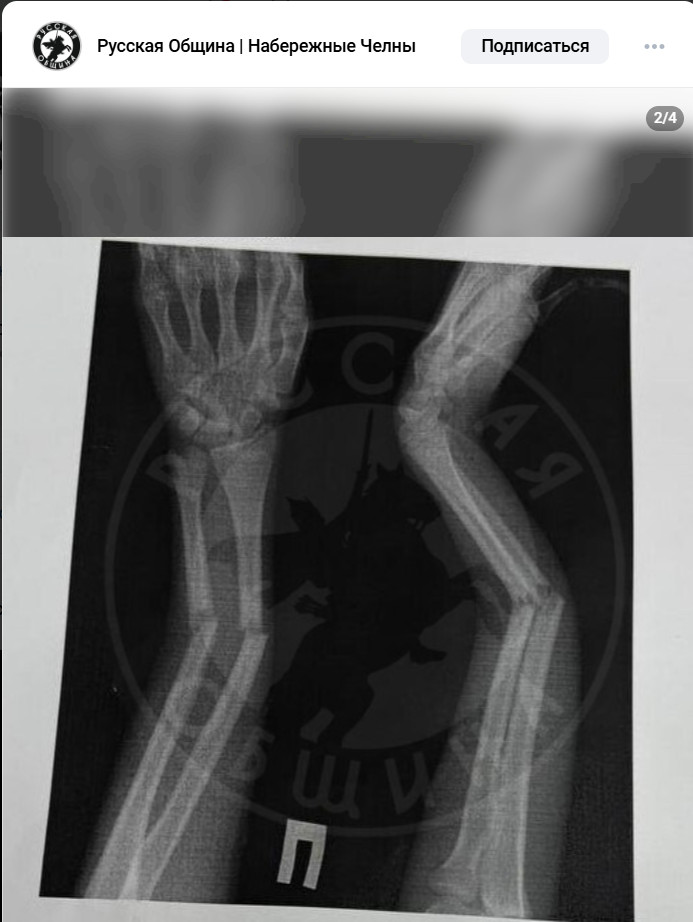

Девочка не стала отвечать на провокацию и попыталась уйти, но сын Абдурахмона схватили её за руку и со всей силы швырнул на пол. Результат: закрытый перелом обеих рук, экстренная госпитализация и операция под общим наркозом. Врачи не исключают, что для восстановления потребуется установка аппарата Илизарова и длительная реабилитация.